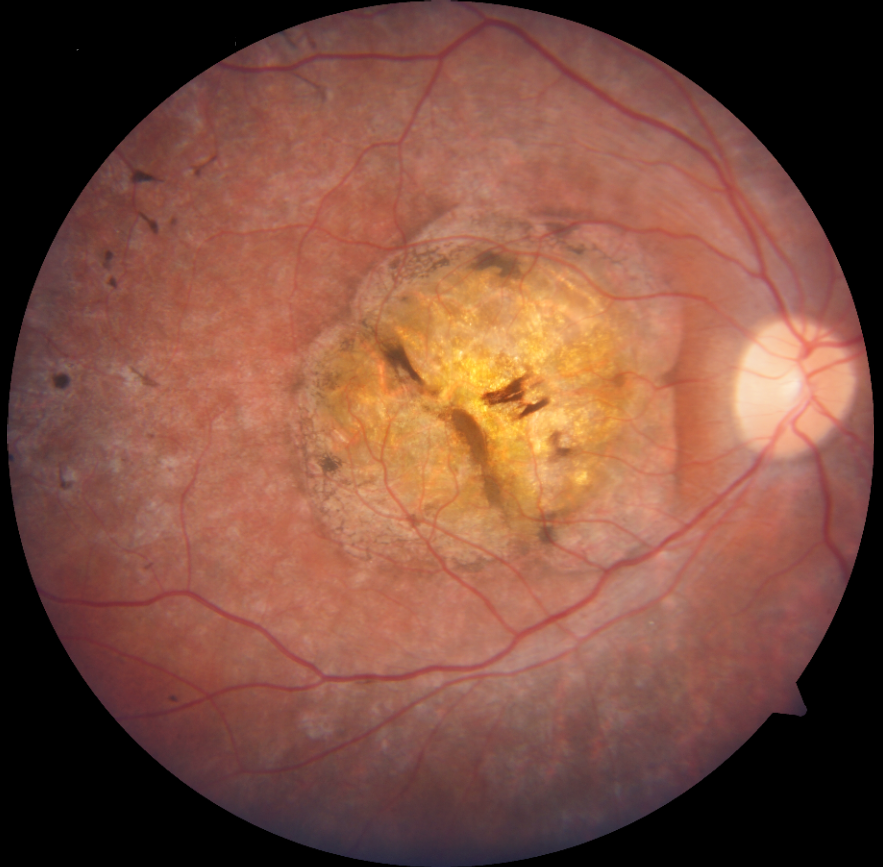

Adölesan Stargardt Hastalığınd ...

Adölesan Stargardt Hastalığında İlk Başarılı Faz 3 Çalışma: Tinlarebant ile Reti ...